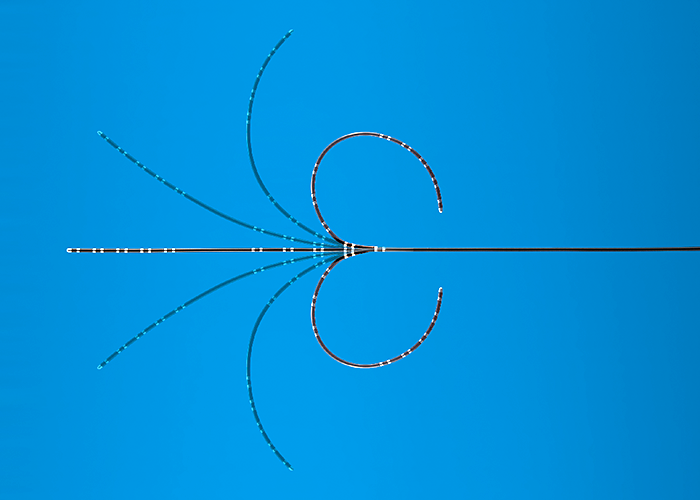

カネカ電極カテーテル(ピッグテール付きタイプ)

- 販売名

- カネカ電極カテーテル

- 医療機器承認番号

- 22900BZX00308000

カネカ電極カテーテル(CS-RAタイプ)

- 販売名

- カネカ電極カテーテル

- 医療機器承認番号

- 22900BZX00308000